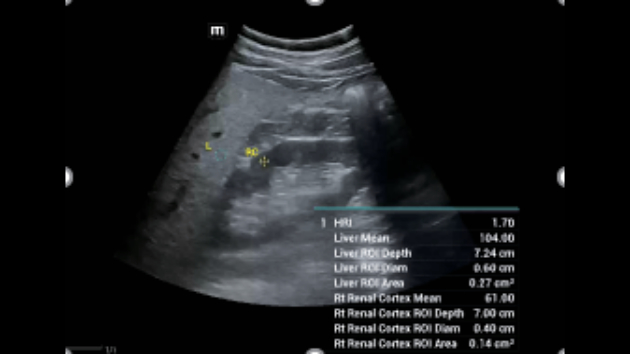

Uitgebreide?oplossingen voor beeldvorming aangestuurd door ZST?+

Het ZST+?platform is een buitengewone innovatie en revolutie in de wereld van echografie. Het transformeert echografiegegevens van conventionele bundelvorming naar kanaalgegevensverwerking. Het overwint de traditionele afweging tussen ruimtelijke resolutie, temporele resolutie en weefseluniformiteit, en levert een uitzonderlijke beeldkwaliteit voor oneindige beeldvormingsoplossingen met non-stop verbeteringen.